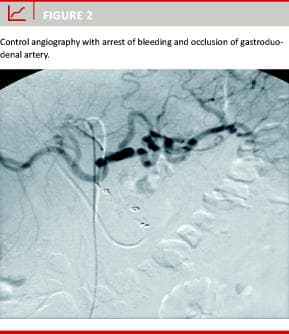

A total of 40 patients underwent embolisation procedures with 100% primary technical success. The patient population comprised 26 men and 14 women. The mean age was 67.4 years (range: 31-92 years). The bleeding causes were duodenal ulcer in 21 patients (52%), gastric ulcer in eight patients (20%), complicated pancreatitis in seven patients (18%) and pancreatic carcinoma in four patients (10%). Comorbid conditions were respiratory in eight patients (28%), cardiovascular in five patients (17%), malignant diseases in two patients (7%), renal failure in three patients (10%), coagulopathy in eight patients (28%) and multiorgan failure in three patients (10%). The gastroduodenal artery was embolised in 36 cases (90%) with coils. In nine cases angiography of the superior mesenteric artery also revealed back-bleeding from the inferior pancreatico-duodenal artery which was also embolised to achieve complete angiographic haemostasis. In one patient, embolisation of the gastroduodenal artery was performed from the superior mesenteric artery because the coeliac trunk had a severe stenosis. In another case, additional microparticles were injected to achieve complete haemostasis. The left gastric artery was embolised in two cases (5%). The splenic artery was embolised in two cases (5%). In all patients angiographic cessation of the bleeding was achieved. In 23 patients (57%), "blind" embolisation was performed. In 15 patients (38%), it was possible to visualize the bleeding artery by angiography (extravasation of contrast) (Figure 1, and Figure 2). In two pati-ents (5%), pseudoaneurysms of the gastroduodenal artery were found. There were two cases (5%) of clinically insignificant inadvertent dislocation of coils distally into hepatic and splenic arteries. No other complications were related to the intervention. Clinical success was achieved in 33 patients (82%). Seven patients (18%) had early re-bleeding within 4.2 days (range: 1-11 days). A second transcatheter embolisation was performed in three of these patients with clinical success. In the remaining four patients, haemostasis was not achieved. The repeat angiographies revealed that previously embolised arteries were non-bleeding, but other vessels were the causes of rebleeding. Thirty-three patients (82%) were discharged after clinical recovery without further surgical or interventional therapy. Four patients (10%) died during hospital stay due to continuous GI bleeding. The mean follow-up period was 13 months (range: 1-31 months). At follow-up there was no clinical suspicion of GI ischaemia in any of the patients. In the group with clinical success, five patients died (15%) from non-bleeding related diseases: prostate carcinoma (n = 1) cholangiocarcinoma (n = 1), cardiac failure (n = 2) and hepatic failure (n = 1) in the follow-up period.